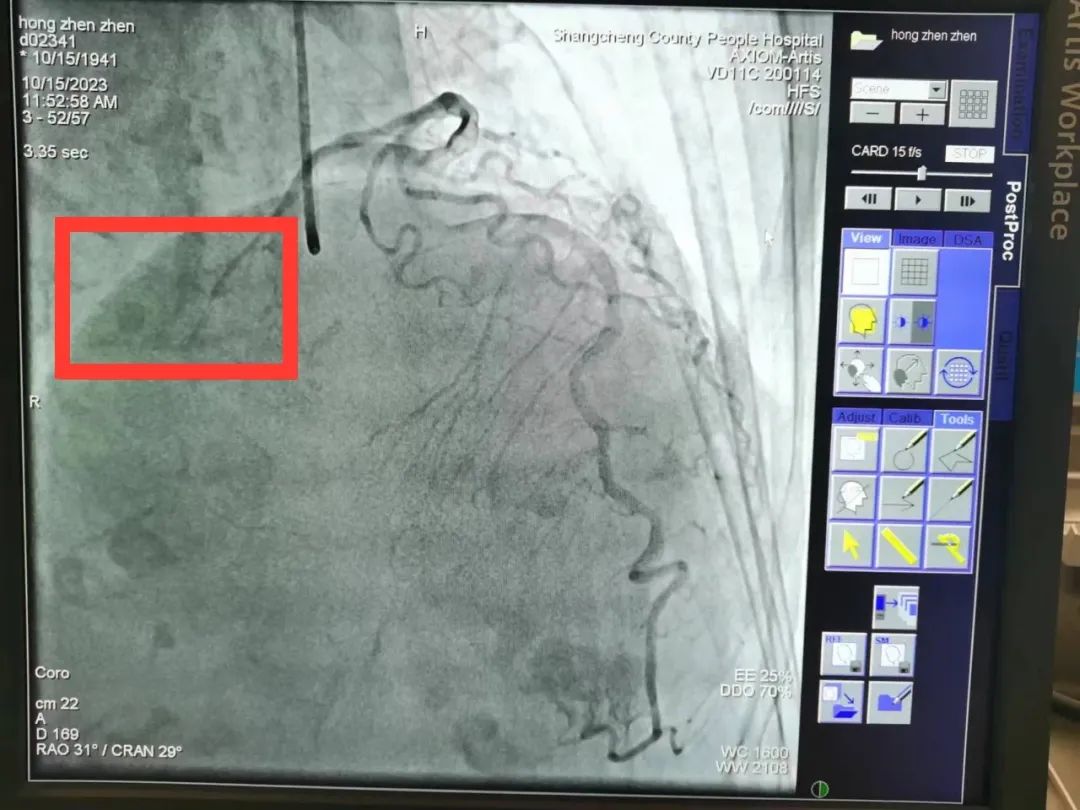

前降支未见明显狭窄